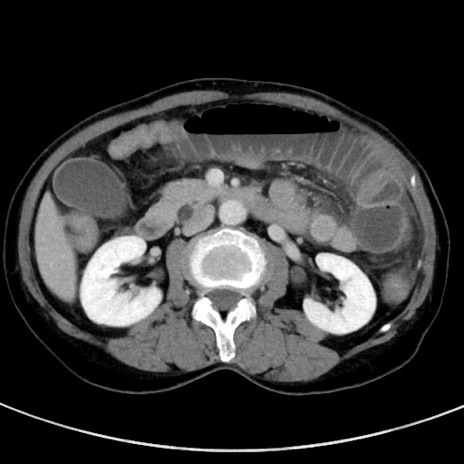

冠状断像

【症例】70歳代女性

【主訴】下腹部痛・嘔吐

【現病歴】2日前より腹痛あり。昨日嘔吐あり。症状改善しないため来院。

【既往歴】胃GISTに対して胃部分切除後。

【身体所見】BT 37.1℃、BP 128/77mmHg、腹部:平坦・軟、下腹部に圧痛あり。

【データ】WBC 10200、CRP 0.31